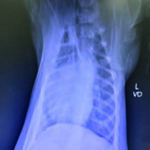

This case study involves a 5-monthsold, intact male Golden Retriever dog presented with tetraparesis, seizure and comatose by a car accident 5 days ago. Physical examination presented unconsciousness, tetraparesis, tachypnea, right temporomandibular joint (TMJ) luxated and crepitus of left humerus. Neurological examination was localized to cerebral cortex and brain stem lesions. The Modified Glasgow Coma Scale (MGCS) was 3. Laboratory tests revealed anemia of 23.1% (reference range, 35-45%), leukocytosis of 19.09 x 103/μL (reference range, 5-14.1 x 103/μL). Radiography was presented to skull fracture, lung hemorrhage (Figure 1) and left humerus fracture (Figure 2).